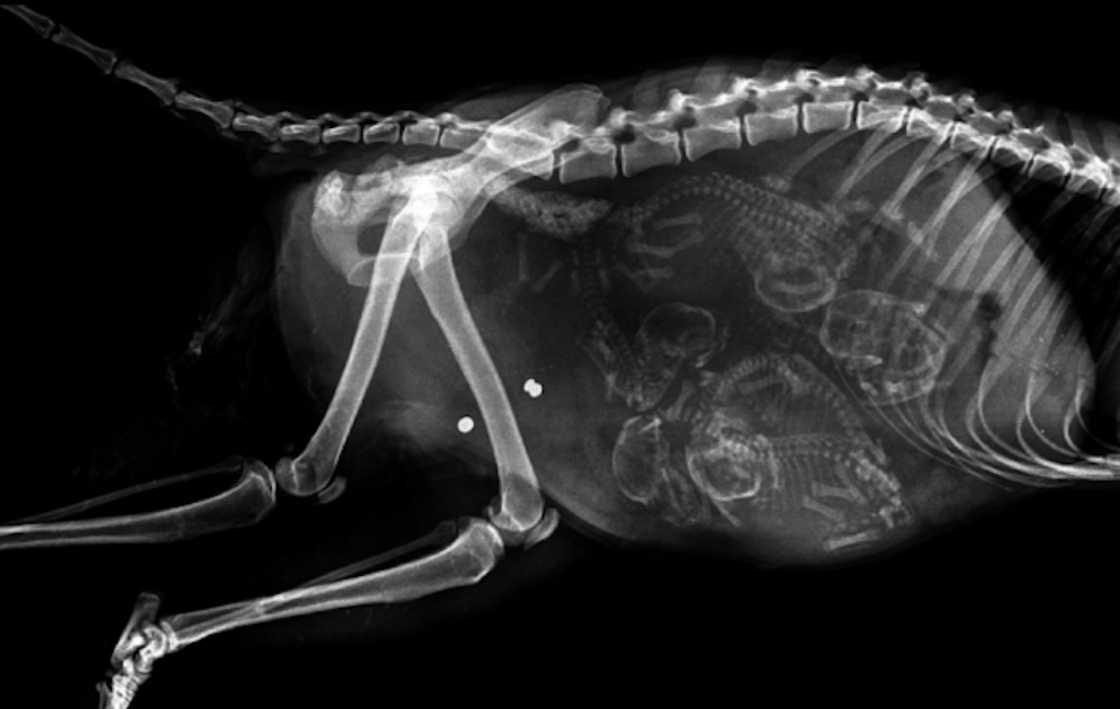

Беременная собака

Как и люди, собаки вынашивают своих детёнышей в течение трех триместров по 21 дню каждый.